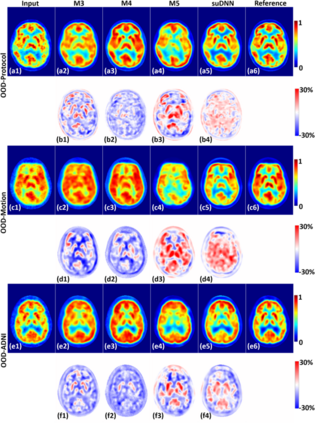

Radiation exposure in positron emission tomography (PET) imaging limits its usage in the studies of radiation-sensitive populations, e.g., pregnant women, children, and adults that require longitudinal imaging. Reducing the PET radiotracer dose or acquisition time reduces photon counts, which can deteriorate image quality. Recent deep-neural-network (DNN) based methods for image-to-image translation enable the mapping of low-quality PET images (acquired using substantially reduced dose), coupled with the associated magnetic resonance imaging (MRI) images, to high-quality PET images. However, such DNN methods focus on applications involving test data that match the statistical characteristics of the training data very closely and give little attention to evaluating the performance of these DNNs on new out-of-distribution (OOD) acquisitions. We propose a novel DNN formulation that models the (i) underlying sinogram-based physics of the PET imaging system and (ii) the uncertainty in the DNN output through the per-voxel heteroscedasticity of the residuals between the predicted and the high-quality reference images. Our sinogram-based uncertainty-aware DNN framework, namely, suDNN, estimates a standard-dose PET image using multimodal input in the form of (i) a low-dose/low-count PET image and (ii) the corresponding multi-contrast MRI images, leading to improved robustness of suDNN to OOD acquisitions. Results on in vivo simultaneous PET-MRI, and various forms of OOD data in PET-MRI, show the benefits of suDNN over the current state of the art, quantitatively and qualitatively.